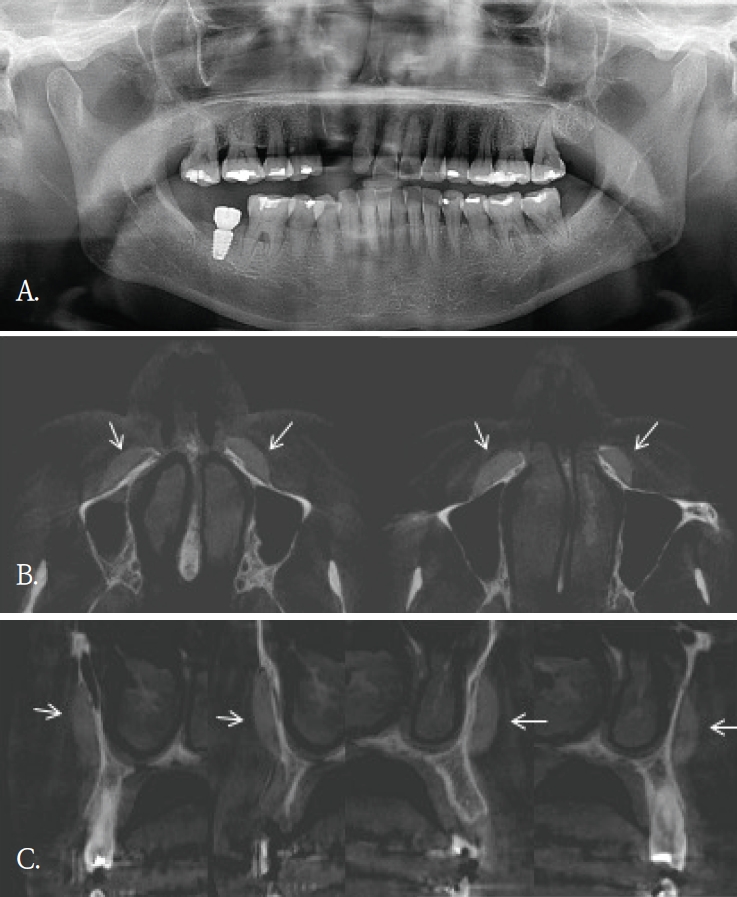

Fig. 3.

A. Panoramic radiograph shows a long, thin, linear radiopaque foreign body along the left mandibular body and inferior border (arrow). B. Coronal cone-beam computed tomographic image demonstrates that the linear radiopaque foreign body is located in the buccal soft tissue lateral to the mandible (arrow).

좌측 안면 부종으로 타원에서 의뢰된 30대 여자환자의 파노라마방사선영상에서 좌측 하악체 및 하연부를 따라 길이가 약 7cm로 측정된, 가는 선 모양의 방사선불투과성 이물질이 관찰되었다(Fig. 3A). 그러나 파노라마방사선영상에서 이물질의 협·설측 위치 및 하악골 내 포함여부를 명확히 판단하기 어려웠다. 이에 위치 및 주변 구조물과의 관계를 평가하기 위해 콘빔CT검사를 시행하였다. 콘빔CT에서 이물질은 좌측 하악체 외측 피질골 바깥의 협측 연조직에서 관찰되었다(Fig. 3B). 영상소견을 바탕으로 구강 내 접근을 통해 외과적 제거술이 시행 되었고 제거된 이물질은 부러진 주사바늘로 확인되었다.

증례 5와 같이 파노라마방사선영상에서 모호하게 관찰되었거나 증례 3과 4같이 파노라마방사선영상에서 협-설위치를 명확하게 알 수 없었던 경우, 콘빔CT영상에서 임상적으로 의미있는 이물질임을 확인되었고 외과적 치료가 시행되었던 증례들이다. 특히, 이들 소견은 악골이 아닌 안면 연조직 부위에서 관찰되어, 주의 깊은 영상판독의 중요성을 다시금 일깨워 준다.